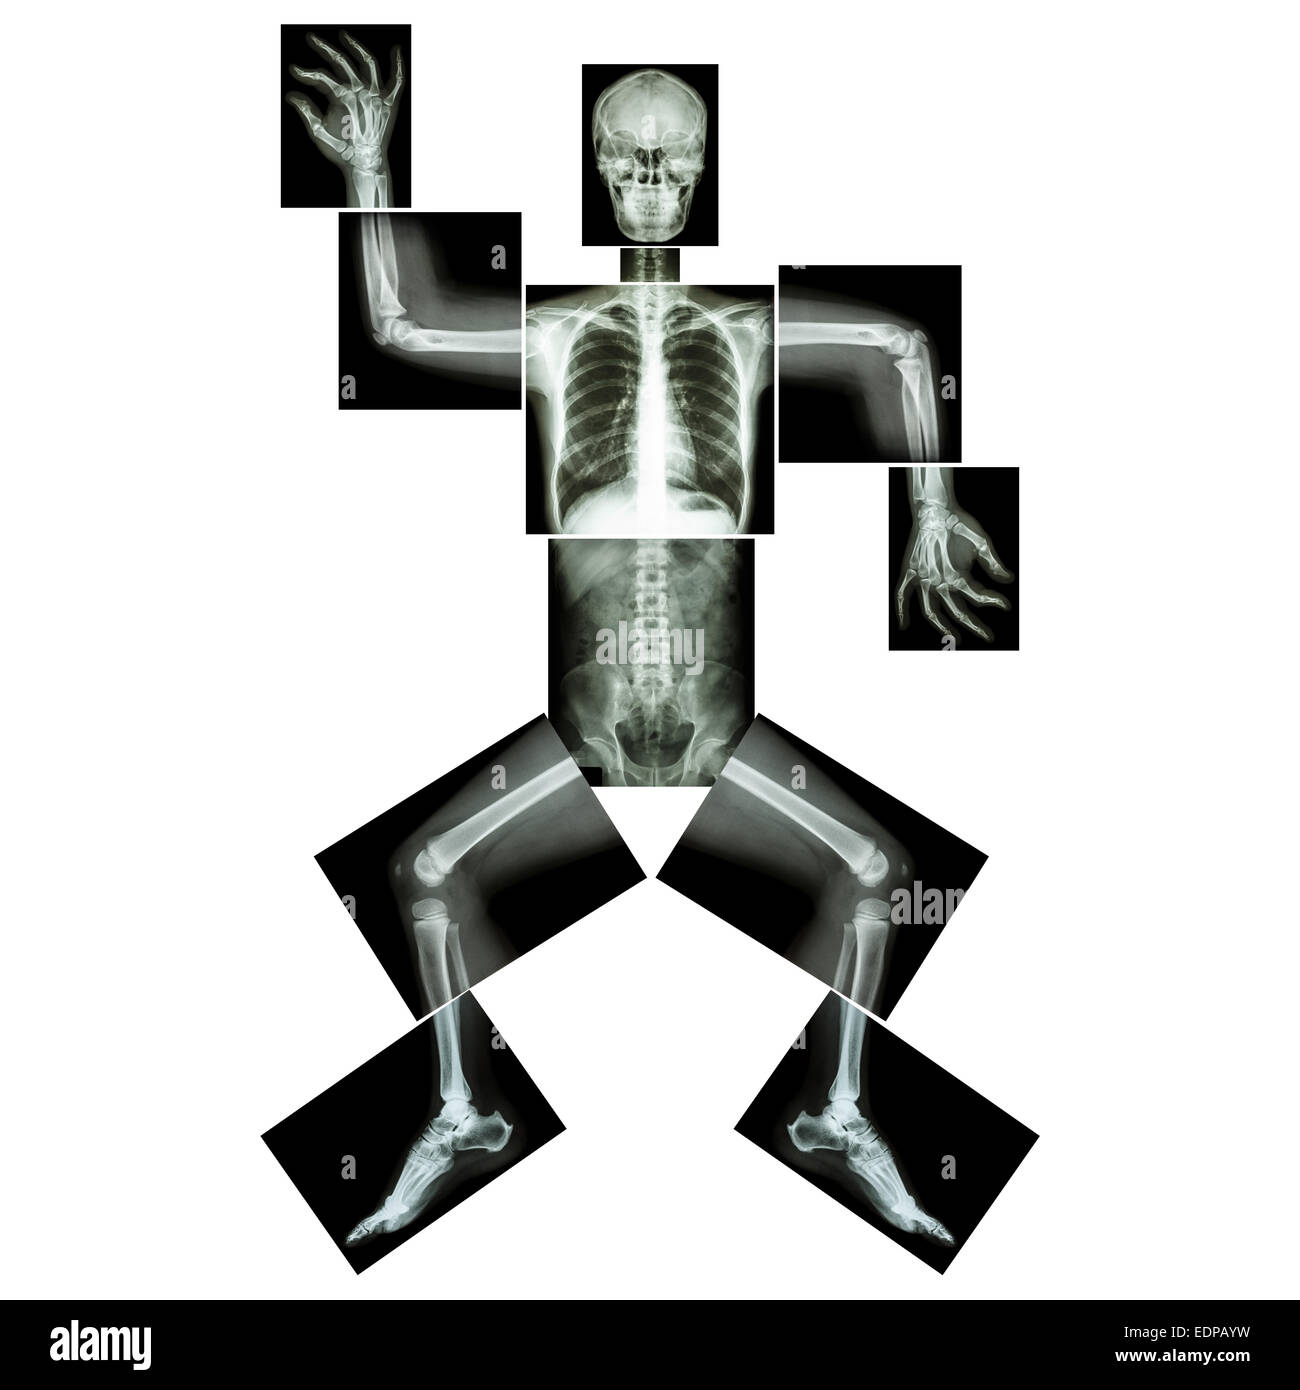

La danse aérobie(os humains est la danse),(corps entier x-ray : tête, cou, thorax, bras, épaule, coude, avant-bras, main, doigt joint , Banque D'Imageshttps://www.alamyimages.fr/image-license-details/?v=1https://www.alamyimages.fr/photo-image-la-danse-aerobie-os-humains-est-la-danse-corps-entier-x-ray-tete-cou-thorax-bras-epaule-coude-avant-bras-main-doigt-joint-77323560.html

La danse aérobie(os humains est la danse),(corps entier x-ray : tête, cou, thorax, bras, épaule, coude, avant-bras, main, doigt joint , Banque D'Imageshttps://www.alamyimages.fr/image-license-details/?v=1https://www.alamyimages.fr/photo-image-la-danse-aerobie-os-humains-est-la-danse-corps-entier-x-ray-tete-cou-thorax-bras-epaule-coude-avant-bras-main-doigt-joint-77323560.htmlRFEDPAYM–La danse aérobie(os humains est la danse),(corps entier x-ray : tête, cou, thorax, bras, épaule, coude, avant-bras, main, doigt joint ,

La danse aérobie(os humains est la danse),(corps entier x-ray : tête, cou, thorax, bras, épaule, coude, avant-bras, main, doigt joint , Banque D'Imageshttps://www.alamyimages.fr/image-license-details/?v=1https://www.alamyimages.fr/photo-image-la-danse-aerobie-os-humains-est-la-danse-corps-entier-x-ray-tete-cou-thorax-bras-epaule-coude-avant-bras-main-doigt-joint-77323562.html

La danse aérobie(os humains est la danse),(corps entier x-ray : tête, cou, thorax, bras, épaule, coude, avant-bras, main, doigt joint , Banque D'Imageshttps://www.alamyimages.fr/image-license-details/?v=1https://www.alamyimages.fr/photo-image-la-danse-aerobie-os-humains-est-la-danse-corps-entier-x-ray-tete-cou-thorax-bras-epaule-coude-avant-bras-main-doigt-joint-77323562.htmlRFEDPAYP–La danse aérobie(os humains est la danse),(corps entier x-ray : tête, cou, thorax, bras, épaule, coude, avant-bras, main, doigt joint ,

La danse aérobie(os humains est la danse),(corps entier x-ray : tête, cou, thorax, bras, épaule, coude, avant-bras, main, doigt joint , Banque D'Imageshttps://www.alamyimages.fr/image-license-details/?v=1https://www.alamyimages.fr/photo-image-la-danse-aerobie-os-humains-est-la-danse-corps-entier-x-ray-tete-cou-thorax-bras-epaule-coude-avant-bras-main-doigt-joint-77323565.html

La danse aérobie(os humains est la danse),(corps entier x-ray : tête, cou, thorax, bras, épaule, coude, avant-bras, main, doigt joint , Banque D'Imageshttps://www.alamyimages.fr/image-license-details/?v=1https://www.alamyimages.fr/photo-image-la-danse-aerobie-os-humains-est-la-danse-corps-entier-x-ray-tete-cou-thorax-bras-epaule-coude-avant-bras-main-doigt-joint-77323565.htmlRFEDPAYW–La danse aérobie(os humains est la danse),(corps entier x-ray : tête, cou, thorax, bras, épaule, coude, avant-bras, main, doigt joint ,

La danse aérobie(os humains est la danse),(corps entier x-ray : tête, cou, thorax, bras, épaule, coude, avant-bras, main, doigt joint , Banque D'Imageshttps://www.alamyimages.fr/image-license-details/?v=1https://www.alamyimages.fr/photo-image-la-danse-aerobie-os-humains-est-la-danse-corps-entier-x-ray-tete-cou-thorax-bras-epaule-coude-avant-bras-main-doigt-joint-77323558.html

La danse aérobie(os humains est la danse),(corps entier x-ray : tête, cou, thorax, bras, épaule, coude, avant-bras, main, doigt joint , Banque D'Imageshttps://www.alamyimages.fr/image-license-details/?v=1https://www.alamyimages.fr/photo-image-la-danse-aerobie-os-humains-est-la-danse-corps-entier-x-ray-tete-cou-thorax-bras-epaule-coude-avant-bras-main-doigt-joint-77323558.htmlRFEDPAYJ–La danse aérobie(os humains est la danse),(corps entier x-ray : tête, cou, thorax, bras, épaule, coude, avant-bras, main, doigt joint ,